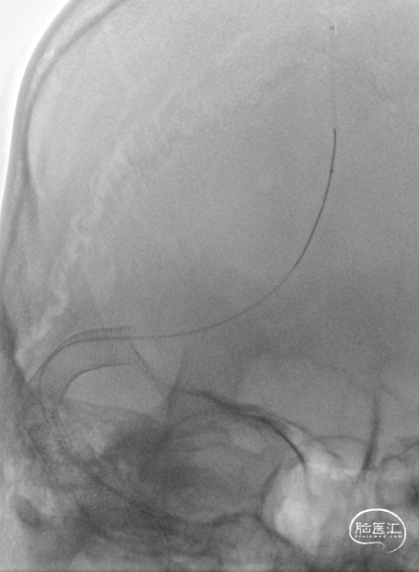

DSA(2022-1-6)

右侧颈总动脉造影示:上矢状窦显影模糊,右侧横窦、乙状窦未见显影,静脉回流缓慢。穿刺右侧颈静脉,留置8F血管鞘,全身肝素化,50万尿激酶入动脉滴注。